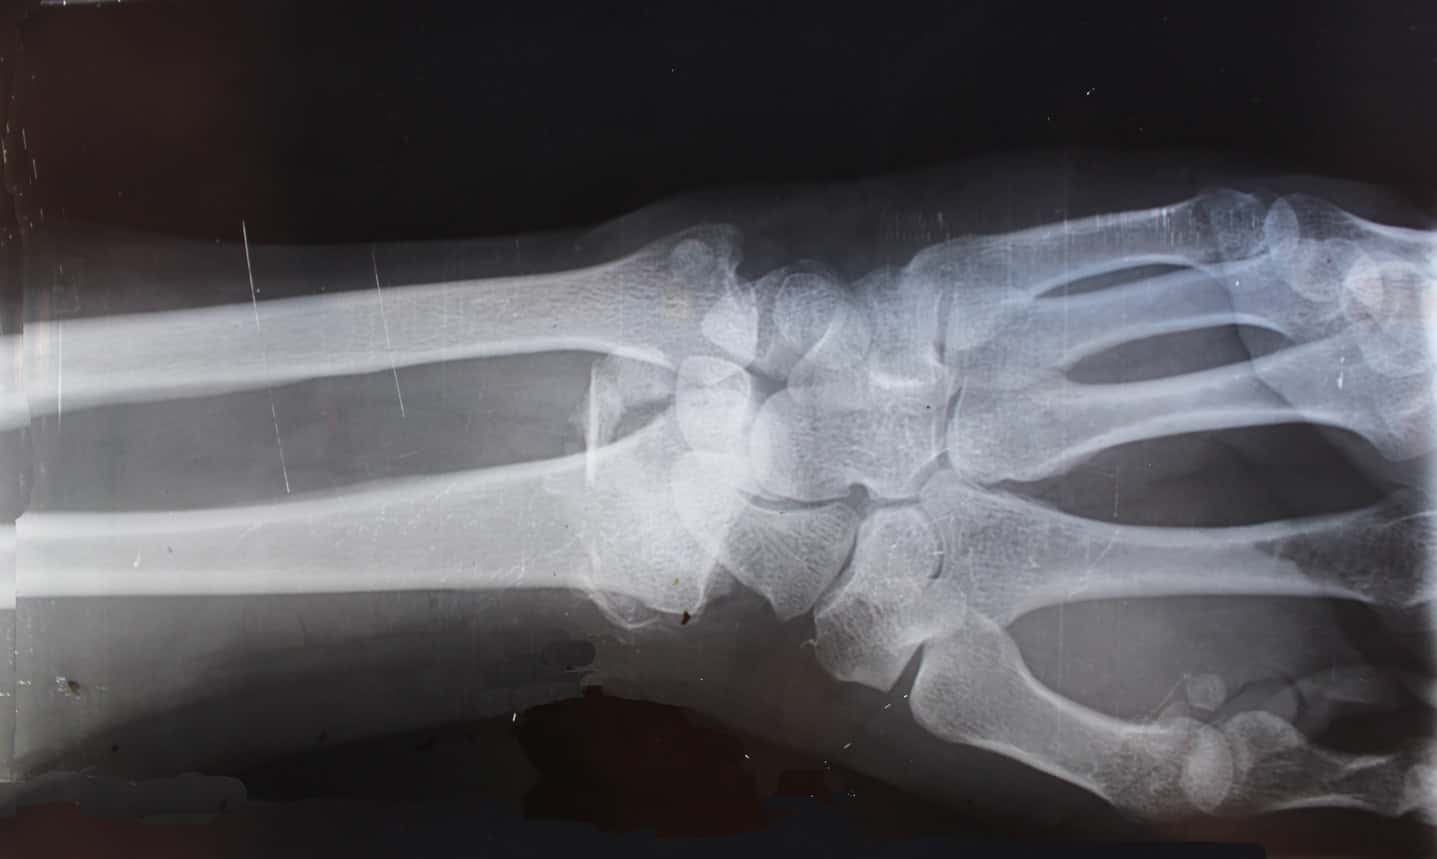

#44 Funny How Life Works

I work in orthopedic surgery. MVA, woman had a shattered hip, bilateral distal radius fractures, multiple rib and lumbar fractures and right sided bimalleolar fracture. Her husband was driving and had a head on collision on HIS side. She somehow took the complete impact of the crash, while he was able to walk away with a few bruises.